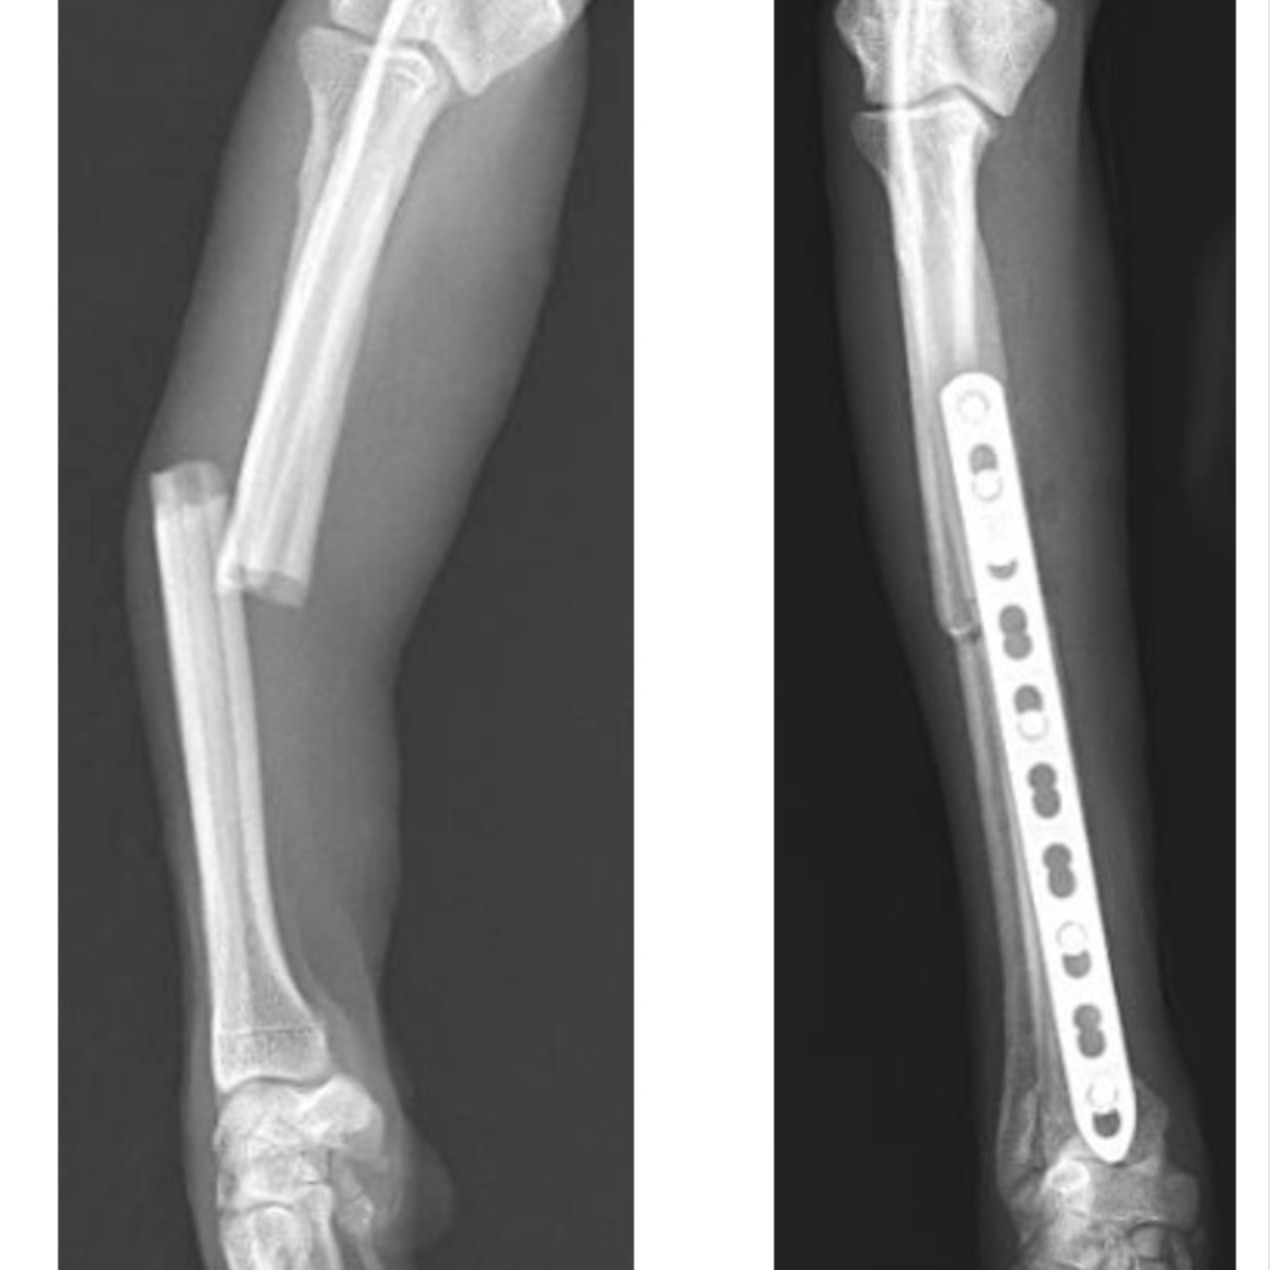

整形外科

本コラムでは獣医療の専門的な情報を取り扱っており、手術中の写真など刺激を受ける可能性のある医療画像を含む場合があります。